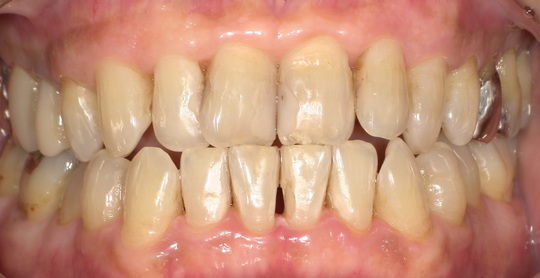

年齢:60代女性

治療内容:エアーフローによる歯の着色汚れ、ステイン除去

治療期間/通院回数:1回

費用: ステインコース 8,800円

リスク・副作用

①効果には個人差があり、着色汚れによっては一度に取りきれない場合があります。

施術後数時間以内に、着色効果の強いもの(コーヒー・紅茶・喫煙など)を摂取すると、歯に色素沈着が起こる可能性があります。

パウダーの刺激により歯ぐきから出血する可能性があります(痛みはほとんどありません)。